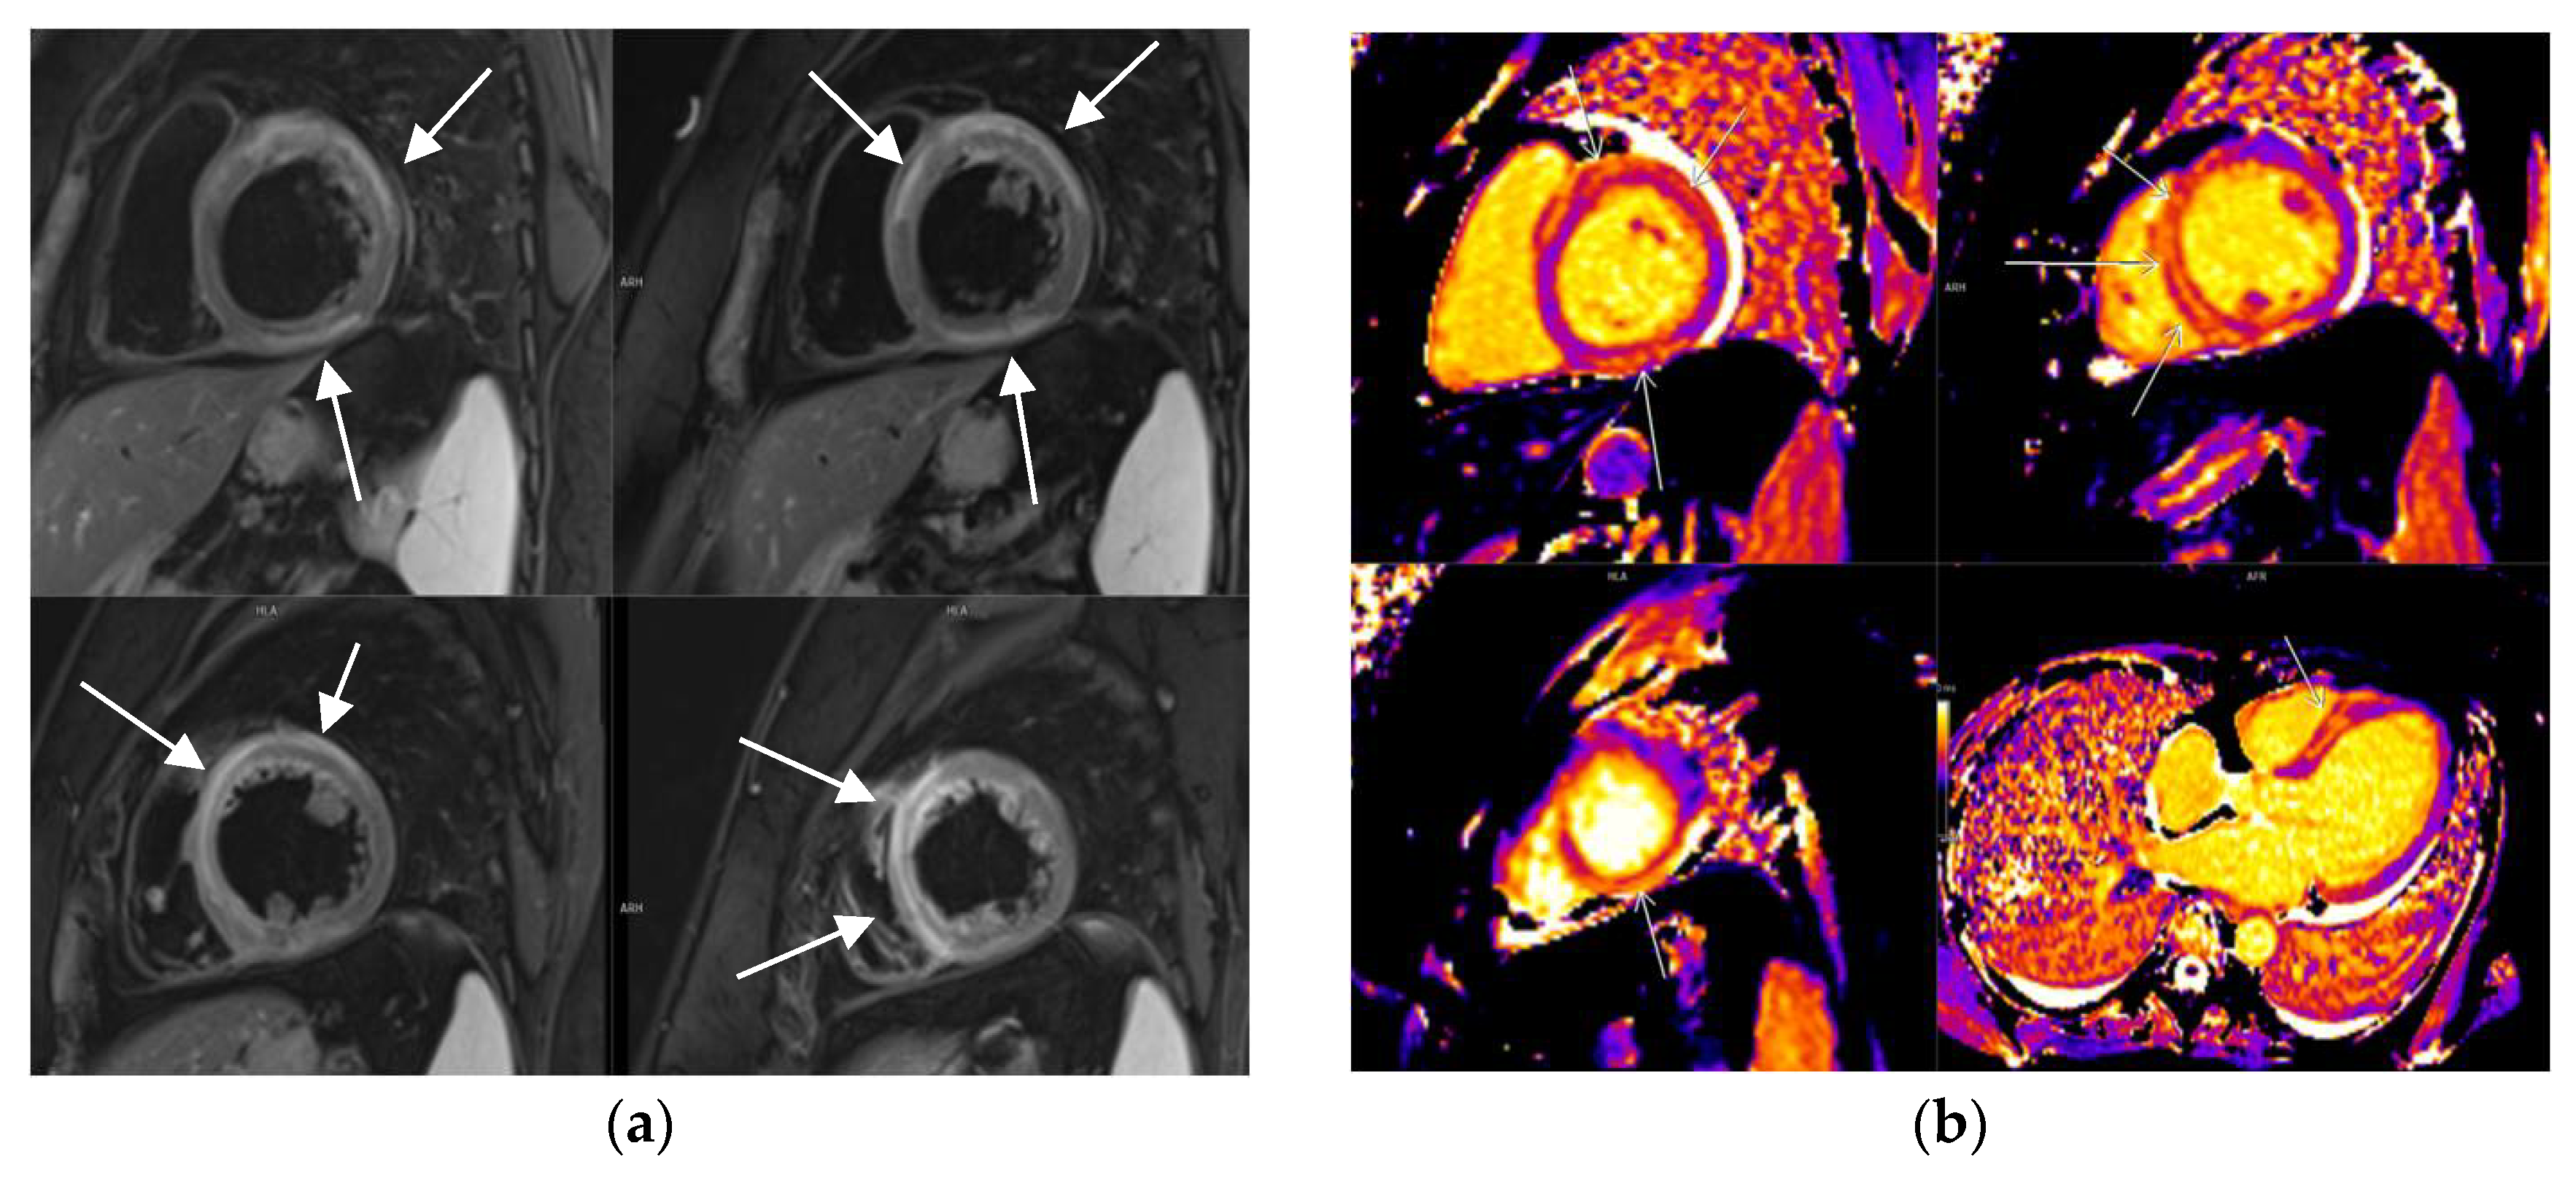

3.2. CMR Findings

3.5. LGE Localization